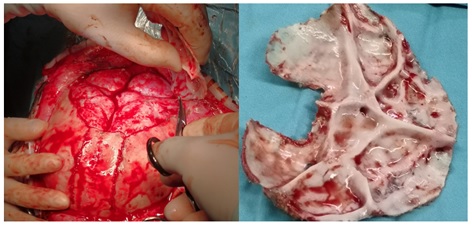

Case 2: Female, 23 months old. Preoperative three-dimensional CT showed bilateral lambdoid suture craniosynostosis, a flat and dysplastic posterior cranial fossa, and CM. After admission, relevant examinations were completed. Under general anesthesia, expansion and remodeling of the posterior cranial fossa, along with foramen magnum decompression, were performed. Significant improvement in the morphology of the posterior cranial fossa was noted post-surgery (Figure 2).

Figure 2: A. Preoperative images displayed bilateral lambdoid suture craniosynostosis and CM, with a flat posterior cranial fossa; B. CT scans taken on the 7th day post-surgery showed significant improvement in the morphology of the posterior cranial fossa and effective correction of the CM.